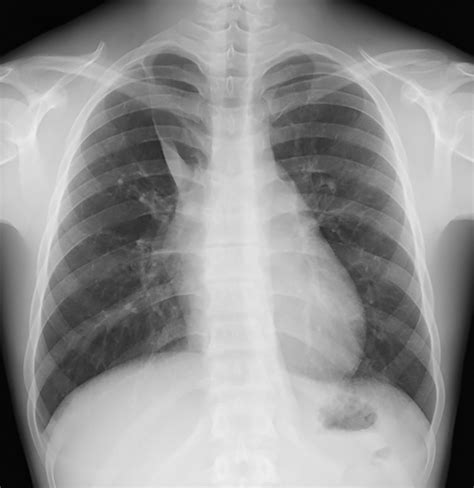

The hallmark of the Vena Azygos Lobe on a chest radiograph is a characteristic curvilinear density. Because of its unique formation, it is easily identifiable if one knows what to look for. Clinicians and radiologists typically identify the following features:

• The Azygos Fissure Line: A thin, convex line extending from the apex of the right lung toward the hilum.

• The Azygos Point (or Teardrop): A dense, teardrop-shaped opacity at the inferior end of the fissure line. This represents the cross-section of the misplaced azygos vein itself.

• Location: Always found in the right upper lobe.

While standard chest X-rays are usually sufficient for diagnosis, computed tomography (CT) provides a definitive view. On a CT scan, the Vena Azygos Lobe is clearly demonstrated as an isolated pleural-lined segment of lung tissue separated from the rest of the right upper lobe by the azygos fissure.